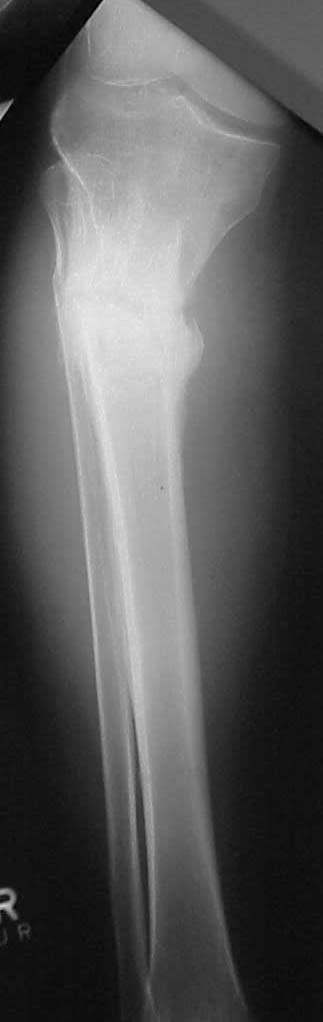

49 yo college professor s/p right proximal tibia fx w/ compartment syndrome. Pt had fasciotomies, ex-fix and delayed percutaneous plating laterally w/ LISS. He had late deep infection at 6 mos and plate removed and fx appeared healed at time. Pt had some varus and deformity, but has collapsed further w/ 25 degrees varus, 15 degrees recurvatum and 20 degrees IR deformity. Lateral wound is healed. ESR and WBCs are normal, 9 mos post injury. Deformity is cosmetically and functionally not acceptable.

Pt was 10 yrs s/p open tibia fx treated in a cast w/ IR, varus, 2 cm short, and recurvatum. He has done well post op.

preop